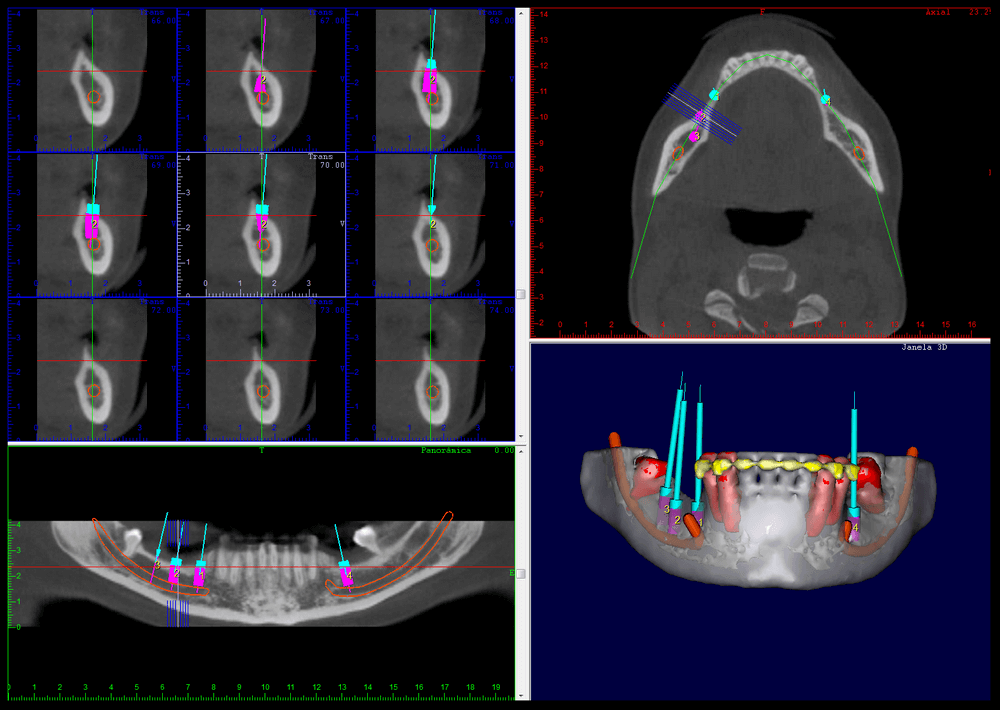

CIRURGIA GUIADA

É uma cirurgia realizada apenas com pequenas perfurações no tecido para instalar os implantes. A partir de um planejamento virtual realizado nos softwares específicos, é feita a confecção de guias cirúrgicas (técnica de prototipagem rápida) e, em seguida, há a transferência precisa do posicionamento dos implantes do computador para o paciente.